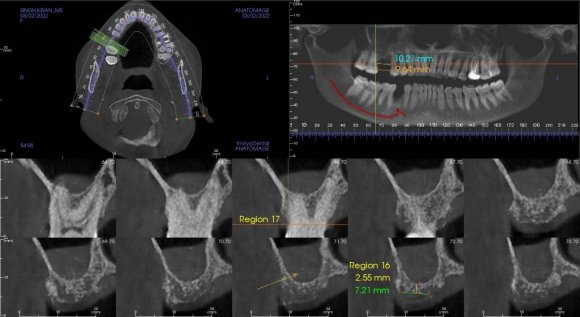

Ils sont placés en regard de la moitié de la hauteur coronaire molaire, ce qui correspond à la hauteur de collage de l'appareil multi-attache.

Ces fils peuvent être insérés sous anesthésie locale (une sédation intraveineuse peut la compléter). L'accès à la branche montante de la mandibule est équivalent à l'accès réalisé pourles extractions des dents de sagesse. Celles-ci sont d'ailleurs souvent extraites lors de l'opération, ce qui permet d'améliorer le recul de l'arcade inférieure donc le redressement incisif.

Une perforation de la branche montante est réalisée, sous irrigation, grâce à une fraise boule montée sur pièce à main chirurgicale, afin de faire passer le fil d'ostéosynthèse de part et d'autre, en protégeant le nerf lingual.